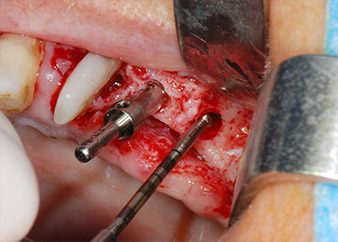

Преди поставянето на импланта, инфектираната тъкан е отстранена от алвеоларната кост в имплантното ложе и около зъба-абатмънт с накрайник, проектиран за оформяне на костта и събиране на костни блокове (Piezomed, накрайник B5) (Фиг. 6 и 7).

Имплантологичното ложе е подготвено в позиции 25 и 26 с ротиращи инструменти, използвайки обратен наконечник 20:1 с усъвършенстван и мощен имплантологичен мотор (Implantmed, W&H) (Фиг. 8).

Следващата препарация близо до синуса отново е извършена с пиезохирургичен накрайник (Piezomed, накрайник S2).